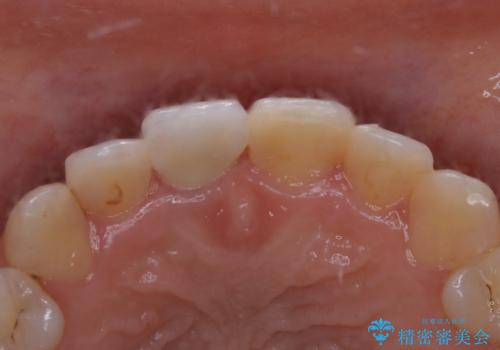

- 前歯一本だけ色が暗いことが気になりご相談にいらした患者様です。周辺の歯と色味をぴったり合わせることで自然な仕上がりになりました。

自費診療で用いられる材料は保険適応の材料に比べて、より精密で適合の良い被せ物作ることができるため、長期的な虫歯のリスクを大幅に減らすことが可能です。